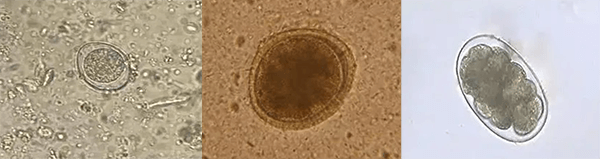

ÄòÒºÆÊÎö

ÄòҺͨÀýÆÊÎöÊÇÈý´óͨÀýÄ¥Á·ÖеÄÒ»Ï×÷ÎªÉøÍ¸Îï¼ì²é£¬ÄòÒºÆÊÎöЧ¹û¿É·´Ó¦»úÌåµÄ´úл״̬£¬ÊÇÐí¶à¼²²¡Õï¶ÏµÄÖ÷ÒªÖ¸±ê£¬Ò²ÊÇÉöÔà»òÄò·¼²²¡µÄÕ÷Õס£²»ÉÙÉöÔಡ±äÔçÆÚ¾Í¿ÉÒÔ·ºÆðÂѰ×Äò»òÕßÄò³ÁÔüÖзºÆðÓÐÐÎÒòËØ¡£